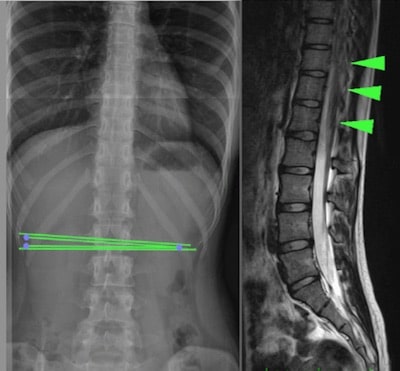

Il midollo ancorato occulto o Occult tethered cord syndrome è associato a una spina bifida occulta, che è una malformazione neuro-spinale che consiste nello sviluppo incompleto del midollo spinale (prevalentemente nella regione lombare), che ancora il midollo spinale e causa lesioni meccaniche da trazione, principalmente midollari e vertebrali (Fig.1).

Per visualizzarla ed effettuare la diagnosi sono necessari esami complementari come la Risonanza Magnetica Nucleare (RMN) o la Tomografia Assiale Computerizzata (TAC) o una radiografia semplice a livello dell’ancoraggio nella colonna vertebrale.